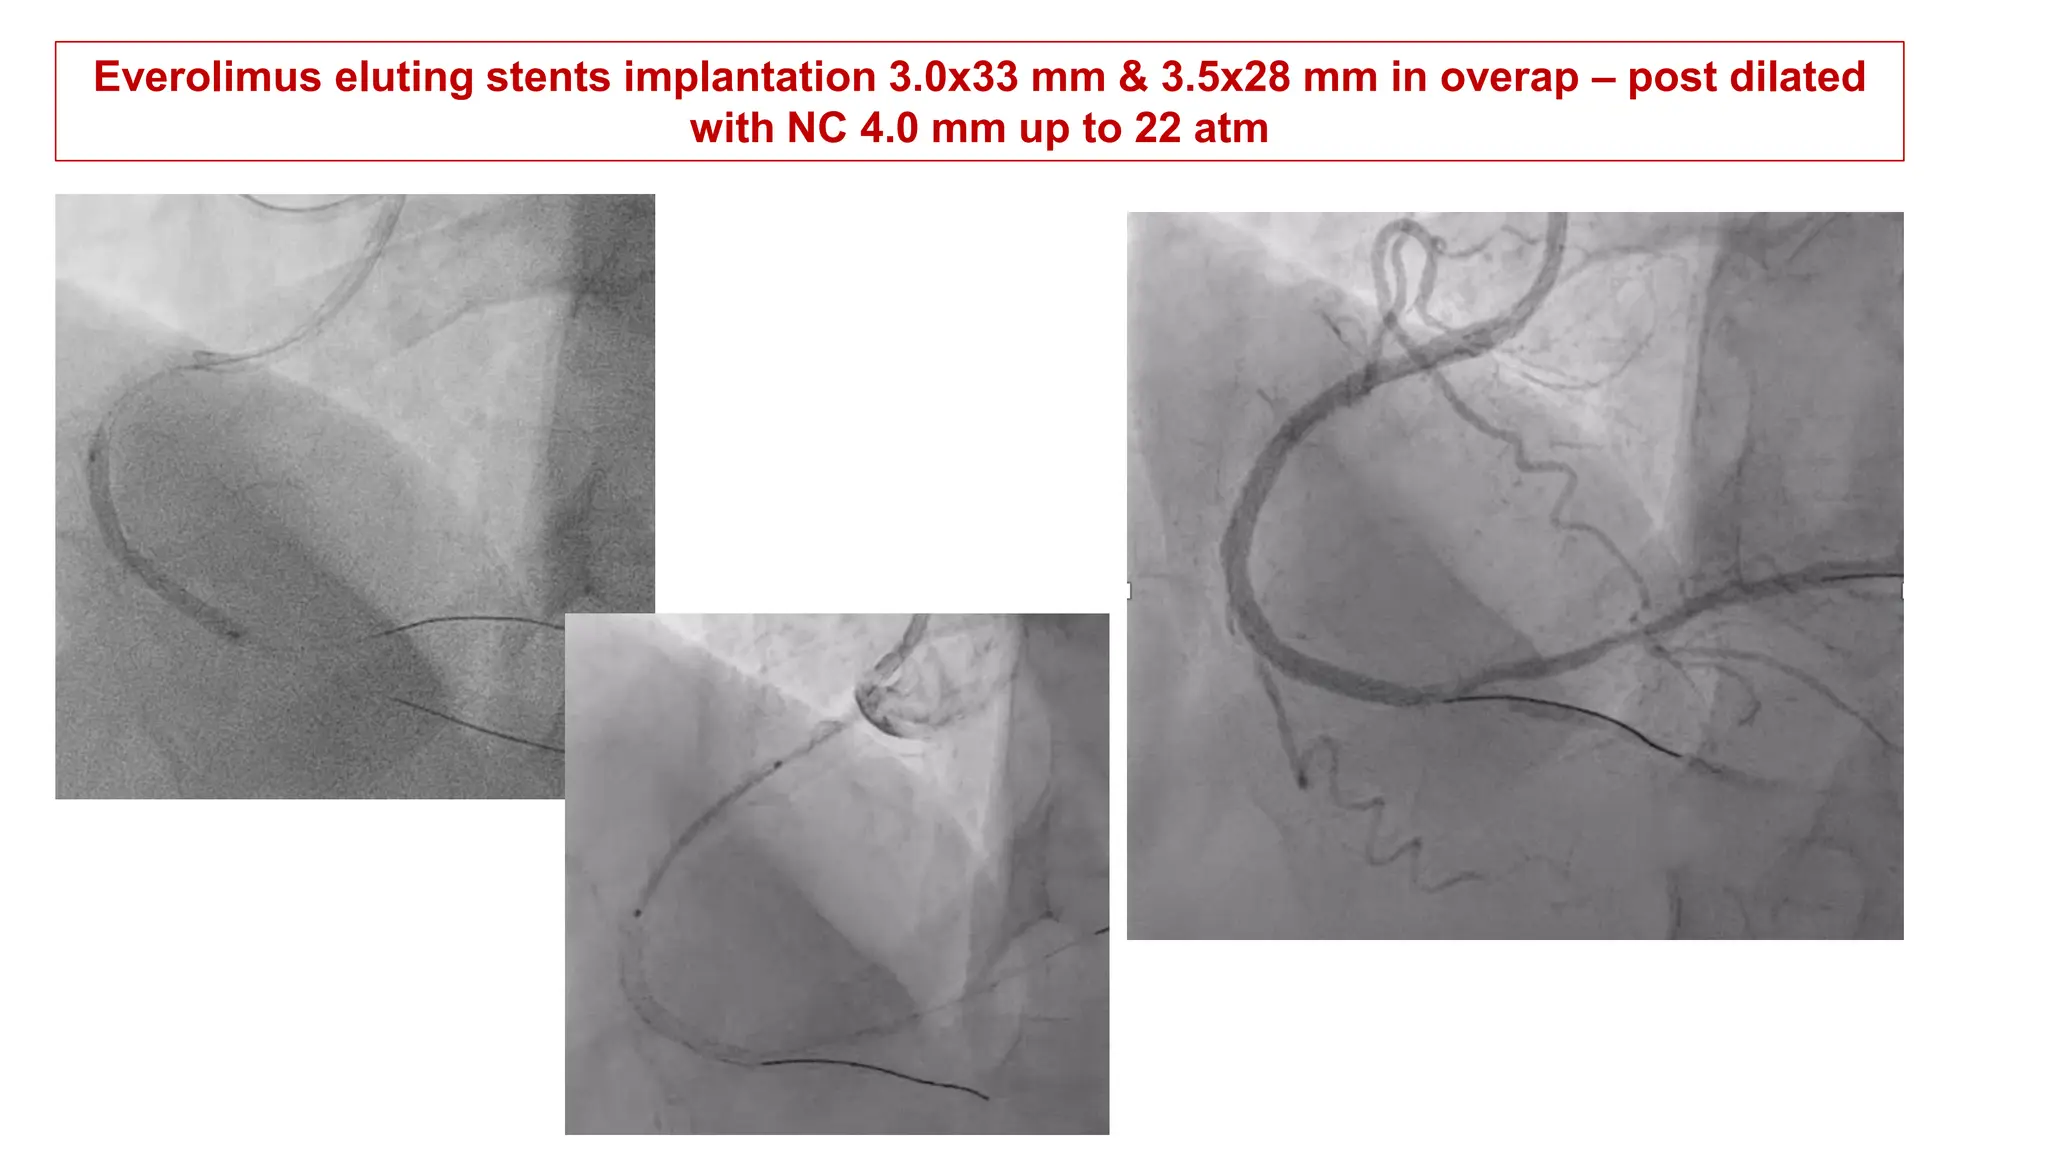

Everolimus eluting stents implantation 3.0x33 mm & 3.5x28 mm in overap – post dilated

with NC 4.0 mm up to 22 atm